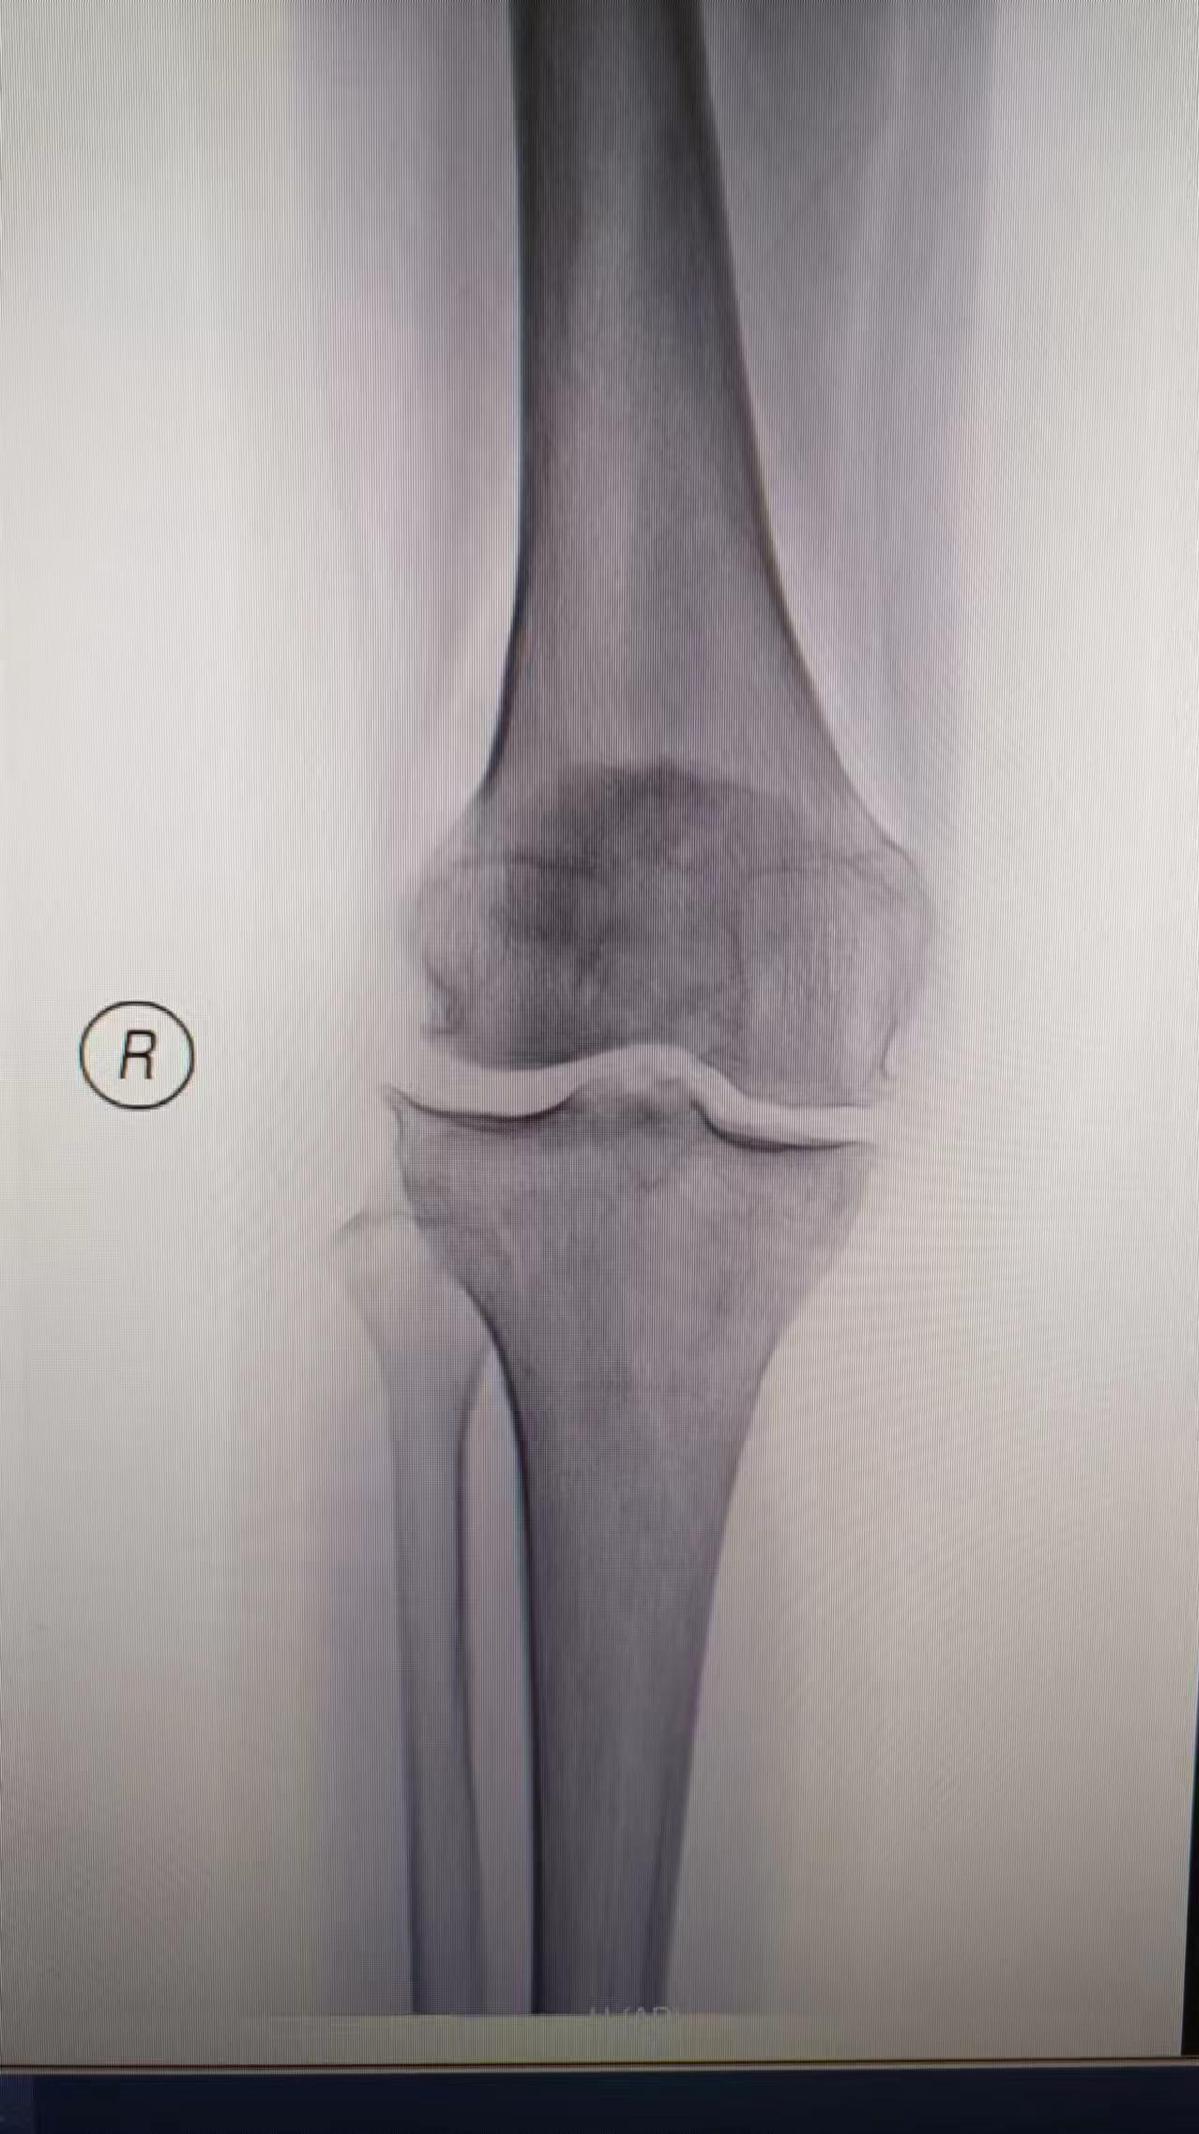

(琼海市人民医院骨关节外科供图)